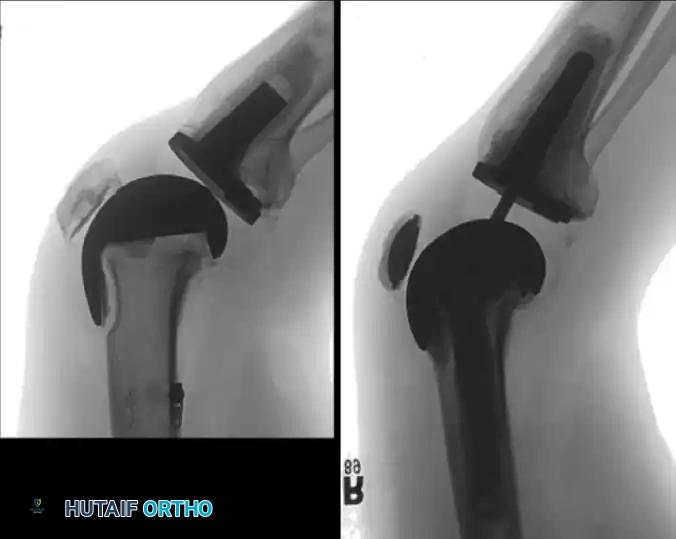

Radiographic Evaluation of the Failed TKA

Meticulous radiographic analysis is the cornerstone of preoperative planning. Aseptic loosening of either component may manifest on standard radiographs as a complete radiolucent line of 2 mm or more at the bone-cement interface in cemented arthroplasties.

Fig. 6-72 Lucency at the entire bone-cement interface of the tibial component, with deformity and subsidence of the component.

Incomplete radiolucencies of less than 2 mm are common and do not necessarily correlate with poor clinical outcomes. However, radiolucent lines around uncemented implants indicate regions where osteointegration has failed. If these lines are extensive, progressive, or symptomatic, aseptic loosening is highly probable.

Fig. 6-73 Loose uncemented femoral component with subsidence into an extended position relative to the distal femur.

Surgical Warning: A radiolucent line under a metal-backed tibial component can be easily obscured by as little as 4 degrees of knee flexion. Fluoroscopic examination is highly recommended for patients with unexplained pain and seemingly "normal" static radiographs. Fluoroscopy allows the x-ray beam to be positioned perfectly parallel to the implant surfaces, unmasking subtle radiolucencies.